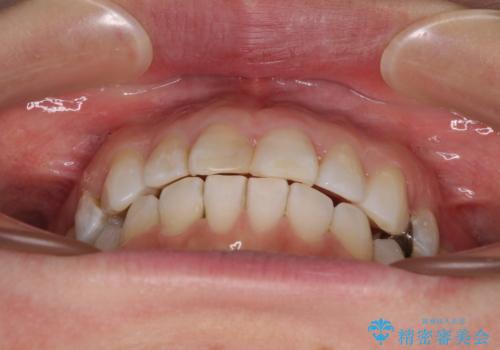

【モニター】前歯のデコボコを治したい インビザラインを用いた矯正治療

- 前歯のデコボコを治したいとのことで来院された患者様です。

上下顎ともに歯列全体の後方移動とIPR(歯と歯の間を削る)によってデコボコが解消するように設計し、インビザラインにより治療を行うこととしました。

しっかりと装着時間を守ってくださったのですが、途中妊娠にともなう悪阻や出産といったイベントがあり、予定よりも治療期間が長くなりました。